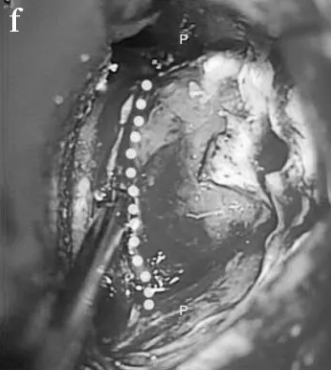

STEP 01:暴露乙状窦和横窦,进行乙状窦后入入路

STEP 02:中部的肿瘤部分被一层很薄的骨板覆盖,骨板被钻掉,虚线显示了骨切除量,这部分最初被移除。

STEP 03:对CPA区肿瘤部分进行内部切除。

STEP 04:肿瘤已完全切除,解除脑干压迫。

STEP 05:面神经被肿瘤浸润, 在图像上可以看到近端、残端有一些附着的肿瘤(箭头)。

STEP 06:重建近端(k)和远端(l)神经残端(PS近端残端,DS远端残端)

STEP 07:准备合适长度的移植体(m), 并用纤维蛋白胶(n)固定到残端,脂肪用于防止脑脊液泄漏(o)。

尽管无法识别神经纤维,但电刺激整个内侧肿瘤部位可激发动态的面部肌电图反应,这也证实肿瘤并非术前的听神经瘤,而是面神经鞘瘤。同时,考虑到Elsa的年龄较小,代偿能力较强,在CPA区的面神经重建术后,面部功能恢复程度非常高,而一旦残余肿瘤,孩子很可能会反复复发,不得不多次手术或放化疗,备受折磨。因此,在权衡各方利弊后,巴教授决定牺牲面神经,最终成功实现了肿瘤全切。

随后,巴教授进行了面神经重建术,将2厘米长的腓肠神经移植桥接到健康的面神经内侧和外侧残端,对面神经功能进行重建。术后13天,Elsa得以恢复出院,无任何新发神经功能缺损,更没有出现面瘫、耳聋等严重后果。12个月后的随访检查显示,她的面神经明显恢复。从此,Elsa又可以重展笑容。